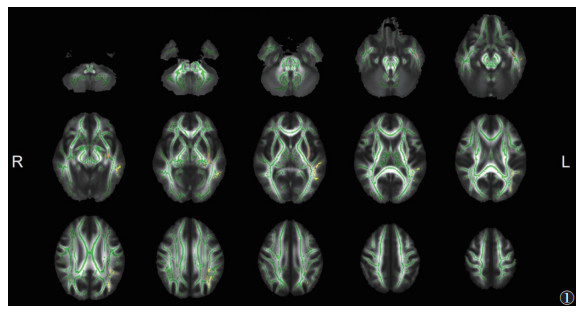

与HC组比,EMTB组脑白质FA未见明显改变,MD在部分脑区升高(P<0.05,TFCE和FWE校正)(图 1),异常MD主要集中在左侧。

| 注:与HC组相比,EMTB组脑白质MD升高的区域显示为暖色(P<0.05,TFCE和FWE校正)。脑白质骨架显示为绿色。L,左;R,右 图 1 颅外多器官结核(EMTB)组与健康对照(HC)组平均扩散系数(MD)的差异 |